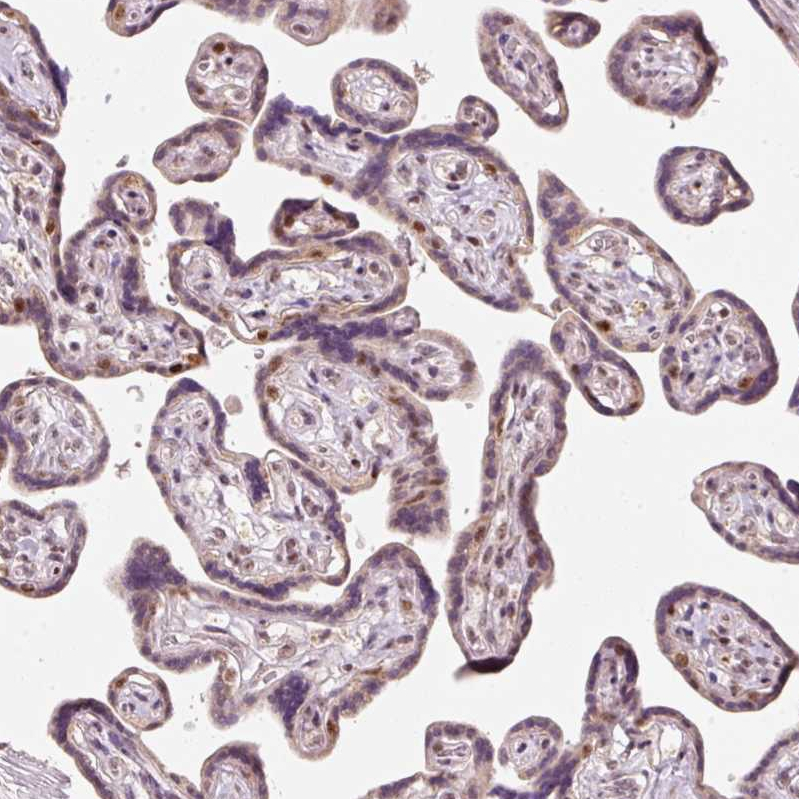

Immunohistochemical staining of human placenta shows strong nuclear positivity in a subset of trophoblastic cells.